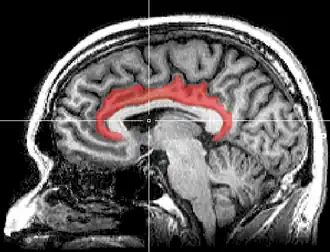

Le gyrus cingulaire est un gyrus du lobe limbique du cortex cérébral. Il est situé sur la face médiale des hémisphères, au-dessus du corps calleux. Au-dessus, il est séparé du gyrus frontal supérieur par le sillon cingulaire et du précuneus par le sillon sous-pariétal. En dessous, sa limite est le sillon du corps calleux. Au niveau du splénium du corps calleux, le gyrus cingulaire se rétrécit dans l'isthme qui se poursuit par le gyrus parahippocampique[1].

On peut diviser le gyrus cingulaire en quatre grandes parties, chacune d'elles accomplissant des tâches spécifiques. Le cortex cingulaire antérieur (CCA) occupe ainsi un rôle dans les états affectifs alors que le cortex cingulaire moyen (CCM) intervient dans le choix des réponses. Le cortex cingulaire postérieur (CCP), quant à lui, tient une place dans la fonction mémorielle. Enfin, le cortex cingulaire rétrospinal (CCR), participe au traitement des informations visuo-spatiales.